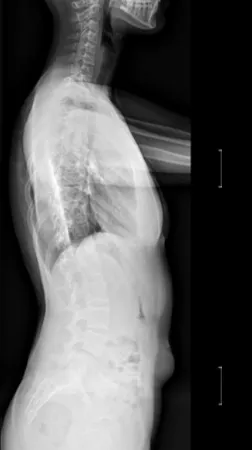

▲ 女,14岁,青少年特发性脊柱侧凸